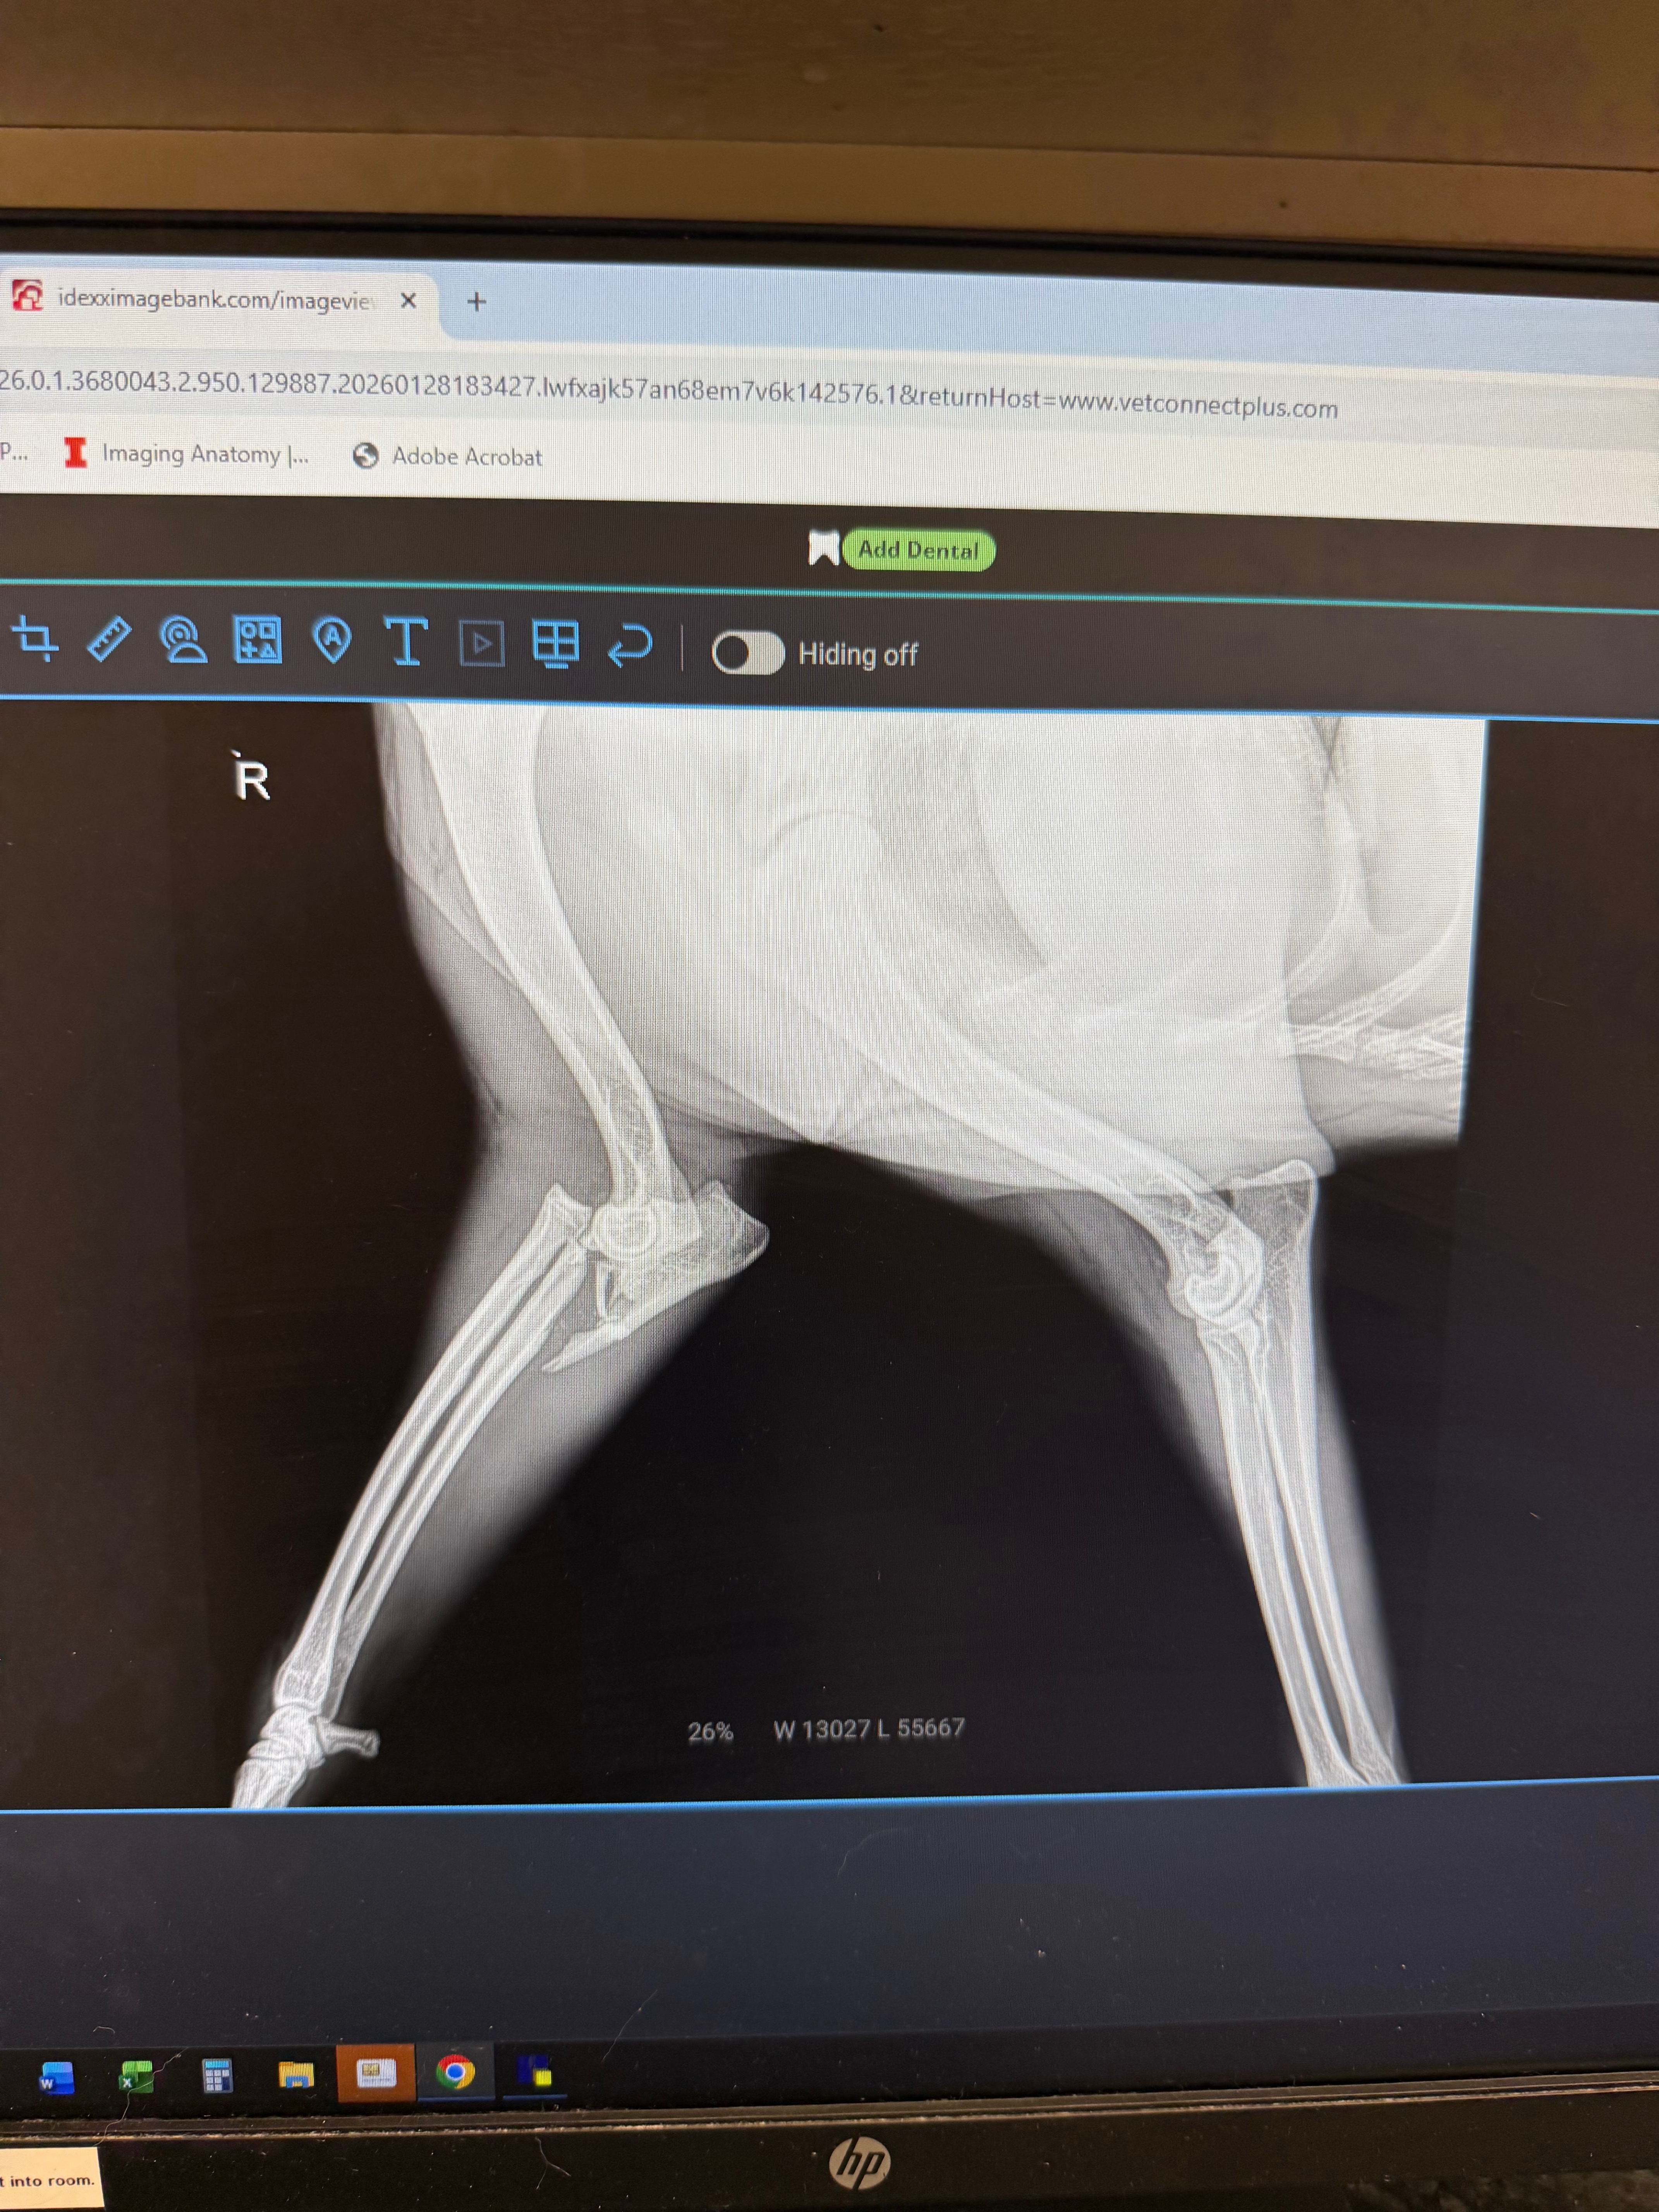

My name is Carmen, And this is my grand dog Moose. Moose was hit by a box truck on 01/28 after he got out of our yard. His first hospital visit cost $800 and that was just for x-rays and we learned he has a broken right front leg.